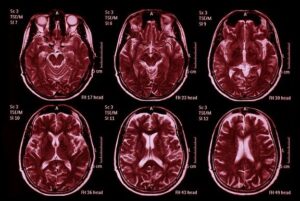

Noticias Médicas: Científicos revelan por qué muchas personas permanecen agotadas tras una hospitalización por COVID-19. Un importante estudio reciente, realizado por importantes instituciones de investigación alemanas, arroja luz sobre por qué tantas personas continúan luchando contra el cansancio crónico y la confusión mental meses después de sobrevivir a una infección grave por COVID-19. Este informe de Noticias Médicas destaca los hallazgos de investigadores de la Charité–Universitätsmedizin de Berlín, la Escuela de Mente y Cerebro de Berlín de la Universidad Humboldt de Berlín, el Hospital Universitario LMU de Múnich, el Hospital Universitario de Würzburg, la Universidad de Colonia, el Centro Médico Universitario de Schleswig-Holstein, la Universidad Justus-Liebig de Giessen, la Universidad Goethe de Fráncfort y varios institutos colaboradores del Centro Alemán de Investigación Pulmonar y el Centro Alemán de Enfermedades Neurodegenerativas. Su trabajo proporciona una de las evidencias más claras hasta el momento de cambios físicos duraderos dentro del cerebro.